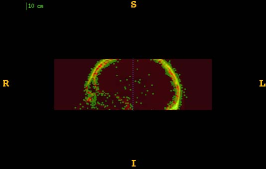

Figure 1 shows the examples of pixel selection masks generated using tested approaches at the highest resolution level for pixel sampling rate 0.5%. It is obvious that the samples generated with the URS approach are extremely spread, whereas the samples generated with the GMS approach are overly concentrated along the gradient magnitude structures present in the image. The proposed approach produces samples that balance those two extremities.